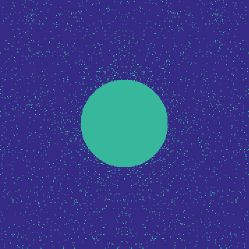

Figure 1 illustrates the best performing randomized indices and our learned set of indices in the plane of the -space. Both the variable density approach [14] and our learning-based approach concentrates its sampling budget on the low frequencies, however the latter is endowed with the capability to adapt its frequency selection to the frequency content of the training signals instead of assuming a circularly symmetric selection.